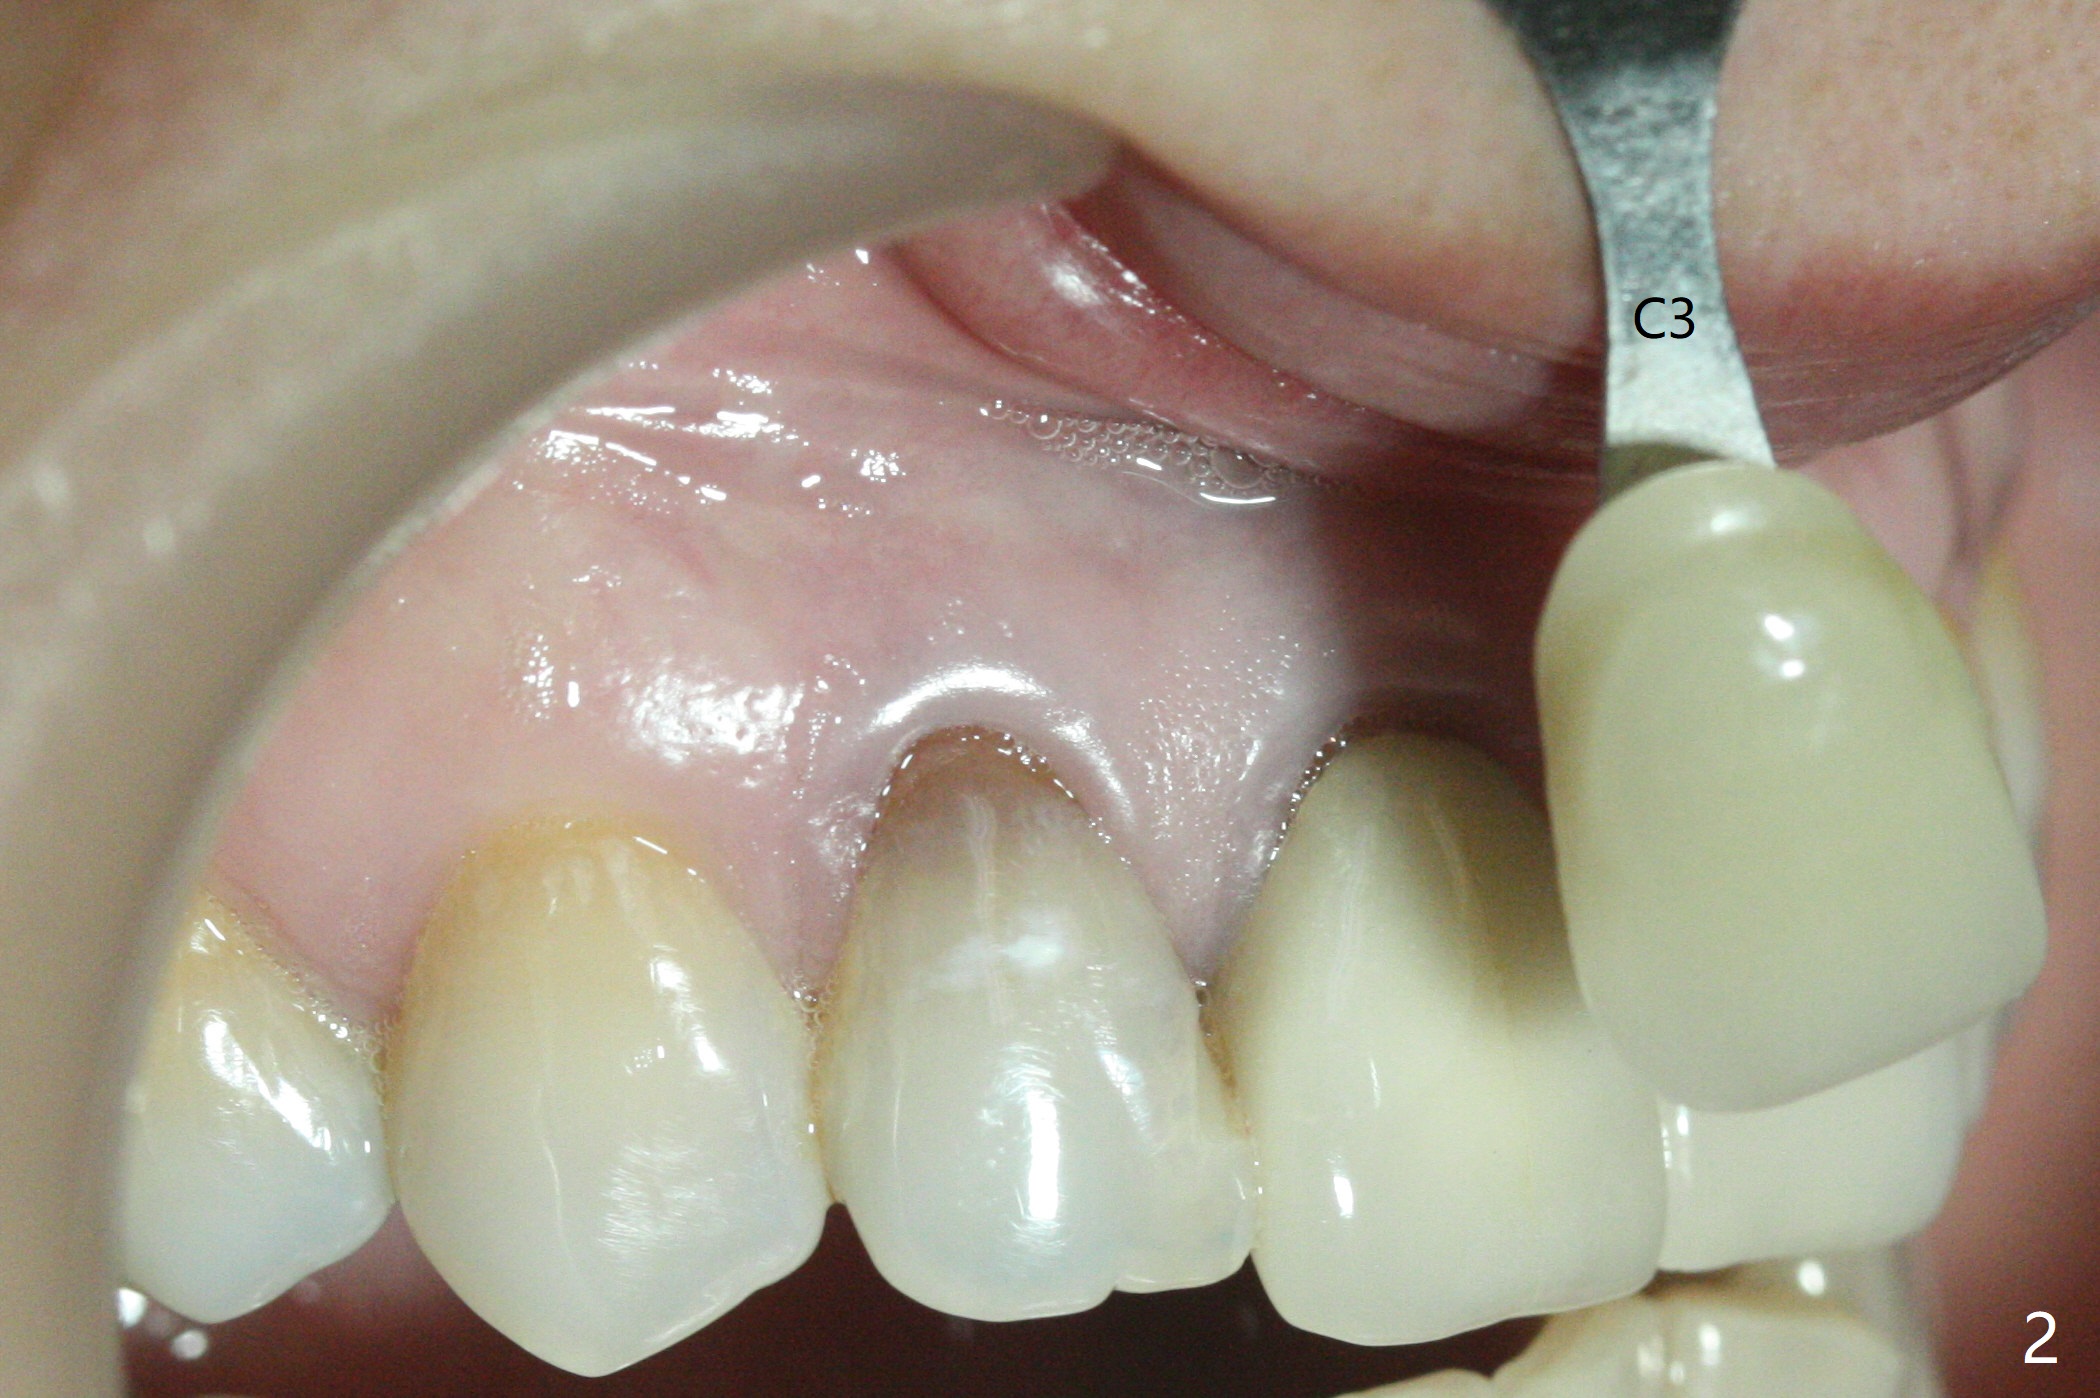

A 46-year-old woman requests a crown for the discolored tooth #7 (Fig.1,2) with mesiolingual composite (Fig.3 C) and periapical radiolucency (*). After RCT (Fig.4,5) with sodium hypochlorite, the tooth #7 is whiter than the ML composite (Fig.6,7). The patient returns 1 day post RCT for in house internal and external bleaching (Fig.8) with 35% hydrogen peroxide gel closed in the canal when she leaves. Three weeks later, the lateral incisor has the shade as the neighboring natural teeth (Fig.9,10). After the lightest shade composite placed in the canal and the access hole (Fig.11), the lateral looks better than the central with a crown and cervical discoloration (Fig.12).